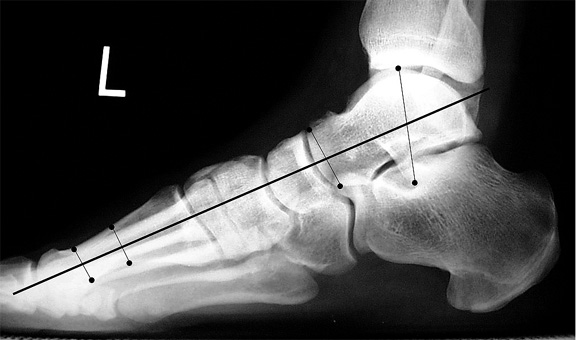

This is an angle formed between the long axis of the talus and first metatarsal on a weight bearing lateral view fig a. Because we had few patients with complete ptt rupture or advanced stage flatfoot deformities in this study it is not surprising that meary angle had the highest association with ptt tear. Hometxt last modified. A calcaneal pitch of less than 170 or 180 indicates flat feet.

Hindfoot valgus where the talocalcaneal angle is 350 talonavicular uncoverage or subluxation. Probably the most familiar line to radiologists and a more direct measurement of pes planus or collapse of the longitudinal arch is the talar 1st metatarsal angle mearys angle 3. Among all the measurements in our study meary angle had the best association with ptt tear as diagnosed on mri. 20160814 0133 external edit page tools.

An angle greater than 40 convex downward is considered a flat foot. Pes planus is a deformity of the foot where the longitudinal arch of the foot is abnormally flattened and can be congenital or acquired. Carrying angle of the elbow. Same lateral x ray showing the measurement of mearys angle which is the angle between the long axis of the talus and first metatarsal bone.